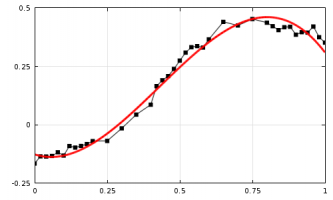

Investigadores del Centro de Salud de la Universidad de Connecticut (UCHC) están explorando aplicaciones de Maple en la interpretación de información de imágenes de resonancia magnética (IRM) para la detección temprana y caracterización de tumores pequeños.

Las redes vasculares necesarias para nutrir el crecimiento en microambientes tumorales pueden ser mucho más densas que en el tejido normal. La densidad vascular es un parámetro importante en la evaluación de la actividad tumoral, pero se reconoce universalmente... |